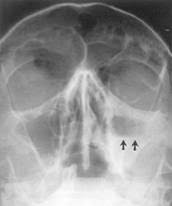

Deci, sinuzita este o sinuzită care se dezvoltă în sinusul maxilar. Sinuzita este o infectie a membranei mucoase care captuseste interiorul foselor nazale si inhalatii cu plante puternic aromate. Sinusurile se impart in patru categorii − etmoidal, frontal, maxilar si sfenoidal − si sunt cavitati mici, pline de aer, care se gasesc in spatele.

Microparticulele de sare uscata cu caracteristici controlate emise de saltmed actioneaza astfel in cazul pacientilor cu sinuzita